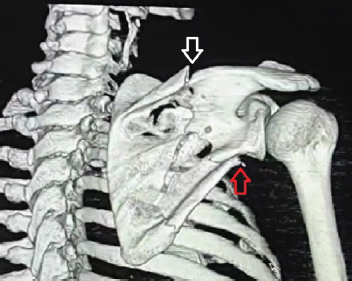

Fixation of Displaced Lateral Column and Spine of Scapula using Modified Judet Approach

Dhruva Angachekar , Samarth Singh , Ashish Singh , Prashik Sirsat , Saurabh Ponde , Padmakar Shine

………………………………p.191-195